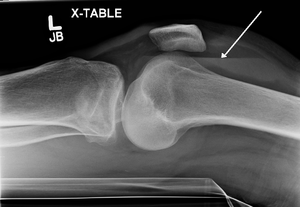

Lipohemarthrosis (presence of fat and blood from bone marrow in the joint space after an intraarticular fracture) seen on X-ray in a person with a subtle tibial plateau fracture

Lipohemarthrosis due to a tibial plateau fracture

Lipohemarthrosis due to a tibial plateau fracture- A tibial plateau fracture seen on X-ray